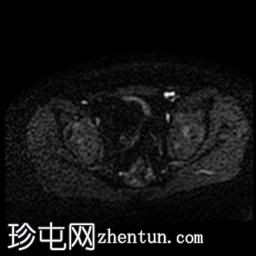

轴位

DWI

MRI序列显示:

女性外生殖器

子宫、宫颈及阴道上2/3缺失

左侧睾丸及腹股沟管内环

右侧睾丸位于腹腔内,靠近腰大肌

双侧卵巢未显影

MRI结果提示雄激素不敏感综合征 (AIS),患者基因构成为男性,但外生殖器为女性(46XY核型)。由于细胞对睾酮等雄激素产生抵抗,雄激素不敏感综合征常伴有双侧隐睾。